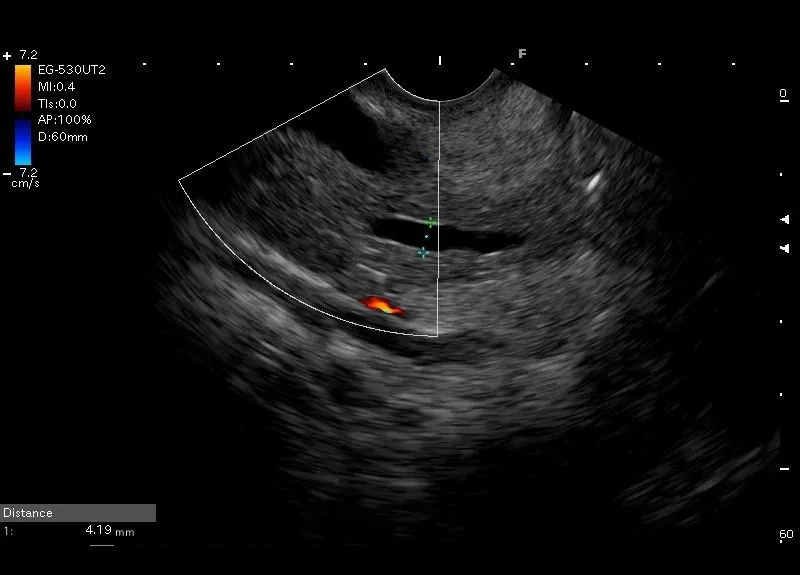

Widoczny w trzonie trzustki przewód szerokości około 4 mm z zaznaczonymi hiperechogenicznymi ściankami, bez widocznego przepływu w opcji Doppler - poszerzony przewód Wirsunga